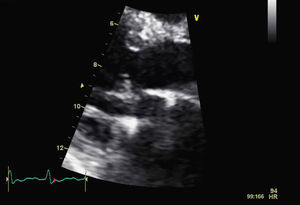

For a more accurate assessment of MV function, TEE was performed (with HR 120–150bpm) (Figures 2 and 3), which showed the MV with a Carpentier ring and leaflet degeneration and redundancy, good opening in diastole but with SAM leading to LVOT obstruction by the anterior leaflet, and severe regurgitation (vena contracta 8mm). The aortic valve was tricuspid, with good opening and mild regurgitation. The left atrial appendage was free of thrombi.